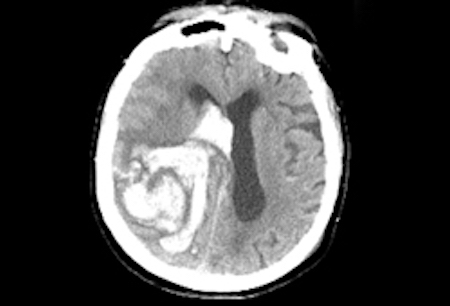

- TC de crânio sem contraste